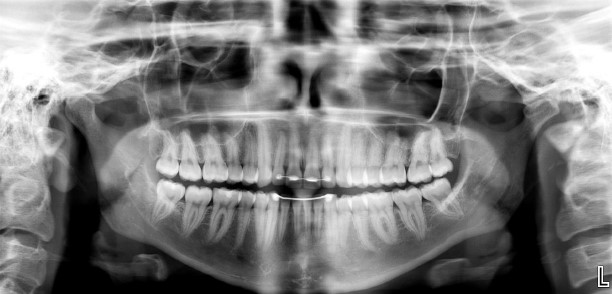

Here, in our beautiful office, we have upgraded to a digital x-ray and left traditional film x-rays in the past. You may be wondering: “What is the difference between the two and the benefits of digital?” The image quality is clear, efficient, quick, and environmentally friendly. Radiation with digital sensors that are more sensitive to X-ray energy and reducing radiation exposure by 70-90 %! With traditional X-rays, there is a longer wait for results, the use of harmful chemicals, and a lack of resolution.